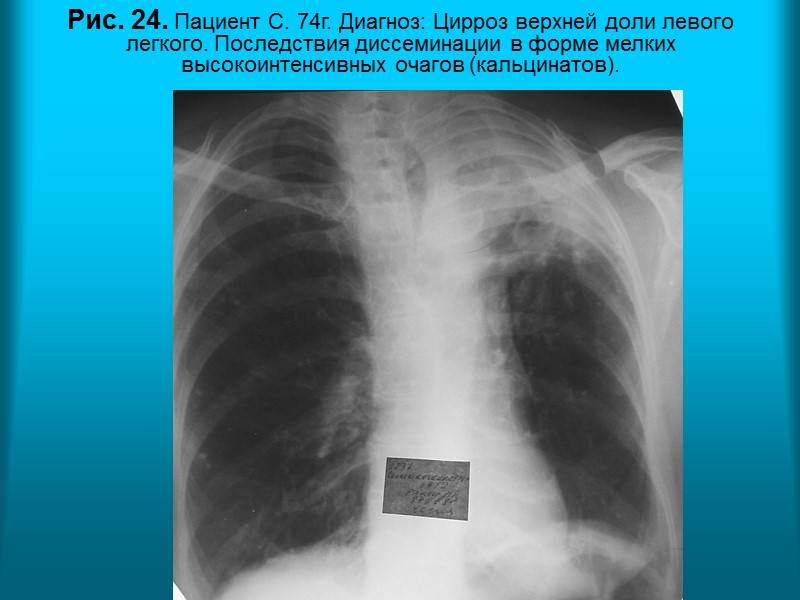

Н.С. Воротынцева. С.С. Гольев Рентгенопульмонология Рис. 24. Пациент С. 74г. Диагноз: Цирроз верхней доли левого легкого. Последствия диссеминации в форме мелких высокоинтенсивных очагов (кальцинатов).